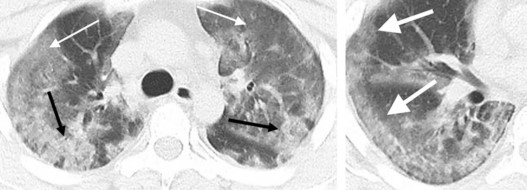

Epidémie de Covid-19 : Point sur l'imagerie

La France est actuellement en situation épidémique de stade 2 vis-à-vis du SARS-Cov-2, et la sollicitation des structures radiologiques, qu'elles soient hospitalières ou non, devient plus importante.

Cette montée en charge nécessite de clarifier le rôle de l'imagerie dans ce contexte épidémique :

1. Quelles sont les indications d'imagerie et quel type d'examen réaliser ?

2. Et quelles précautions prendre pour les manipulateurs et radiologues ?

Imagerie COVID » COVID-19 : Rôle du radiologue Pr Antoine Khalil »